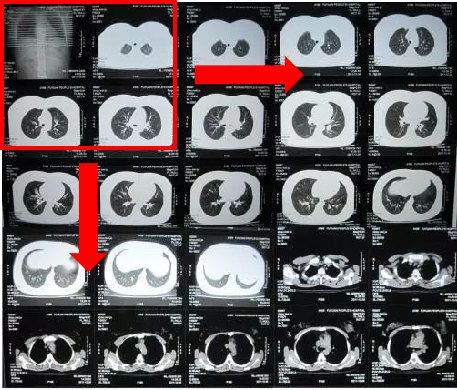

2.把CT片子摆成正确的方向。仔细看看CT片子上的英文字母或者汉字,把字母或者汉字的方向摆正了,CT片子的方向就正确了。我经常收到方向千奇百怪的CT图像,上下颠倒,左右颠倒,甚至正反颠倒,根本不能阅片。按照下面的方向摆,就对了。

3.把手机横过来,给CT片子按照从上到下,从左到右的顺序拍照。一张CT片子,最好分成六次拍照。左上,右上,左中,右中,左下,右下。大部分患者拍照,都是一张CT片子只拍一张照片就传过来了,这样根本看不清楚。排成下图这样的清晰度最好。四个格格一张图,最清楚。